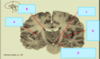

What type of posturing is this person displaying? [1]

Label 5, 6 & 7

1 - superior temporal gyrus; 2 - inferior frontal gyrus; 3 - insular cortex; 4 - temporal stem; **5 - internal capsule;** **6 - thalamus;** **7 - lentiform nucleus** (the internal and external globus pallidus and the putamen) 8 - frontal horn; 9 - superior circular sulcus; 10 - inferior circular sulcus.